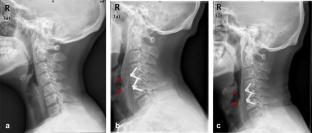

Fig. 1